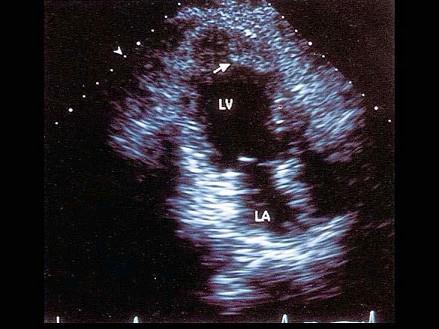

该病例最可能的诊断?(?)A.真性室壁瘤B.假性室壁瘤C.室壁憩室D.扩张型心肌病E.膜部瘤

问题 该病例最可能的诊断?(?)

选项 A.真性室壁瘤 B.假性室壁瘤 C.室壁憩室 D.扩张型心肌病 E.膜部瘤

答案 A